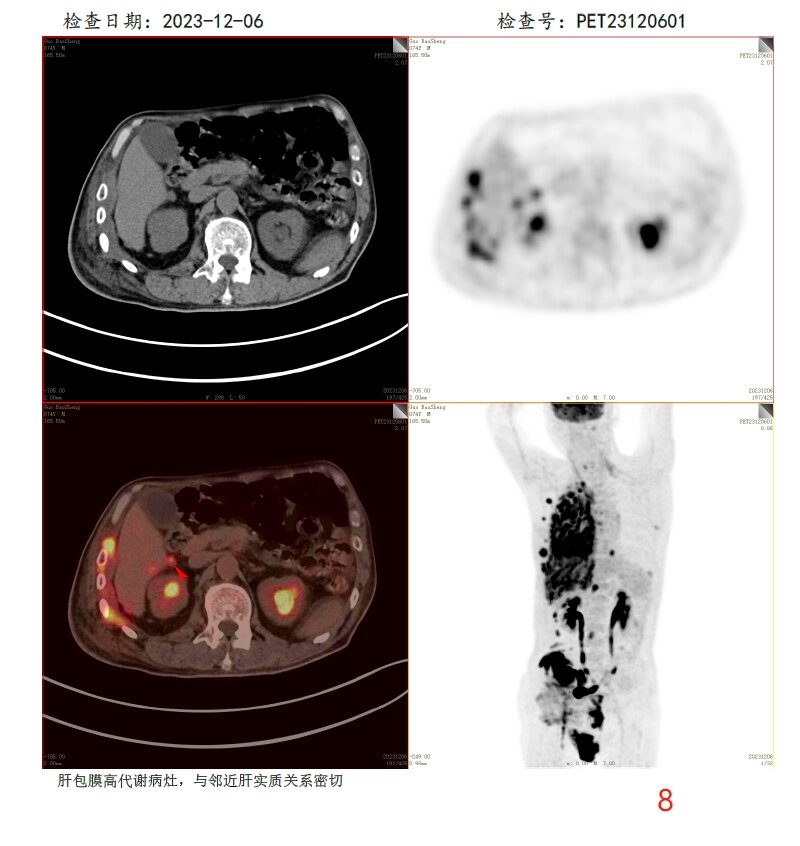

放疗前PET/CT(2023-12-06):

8